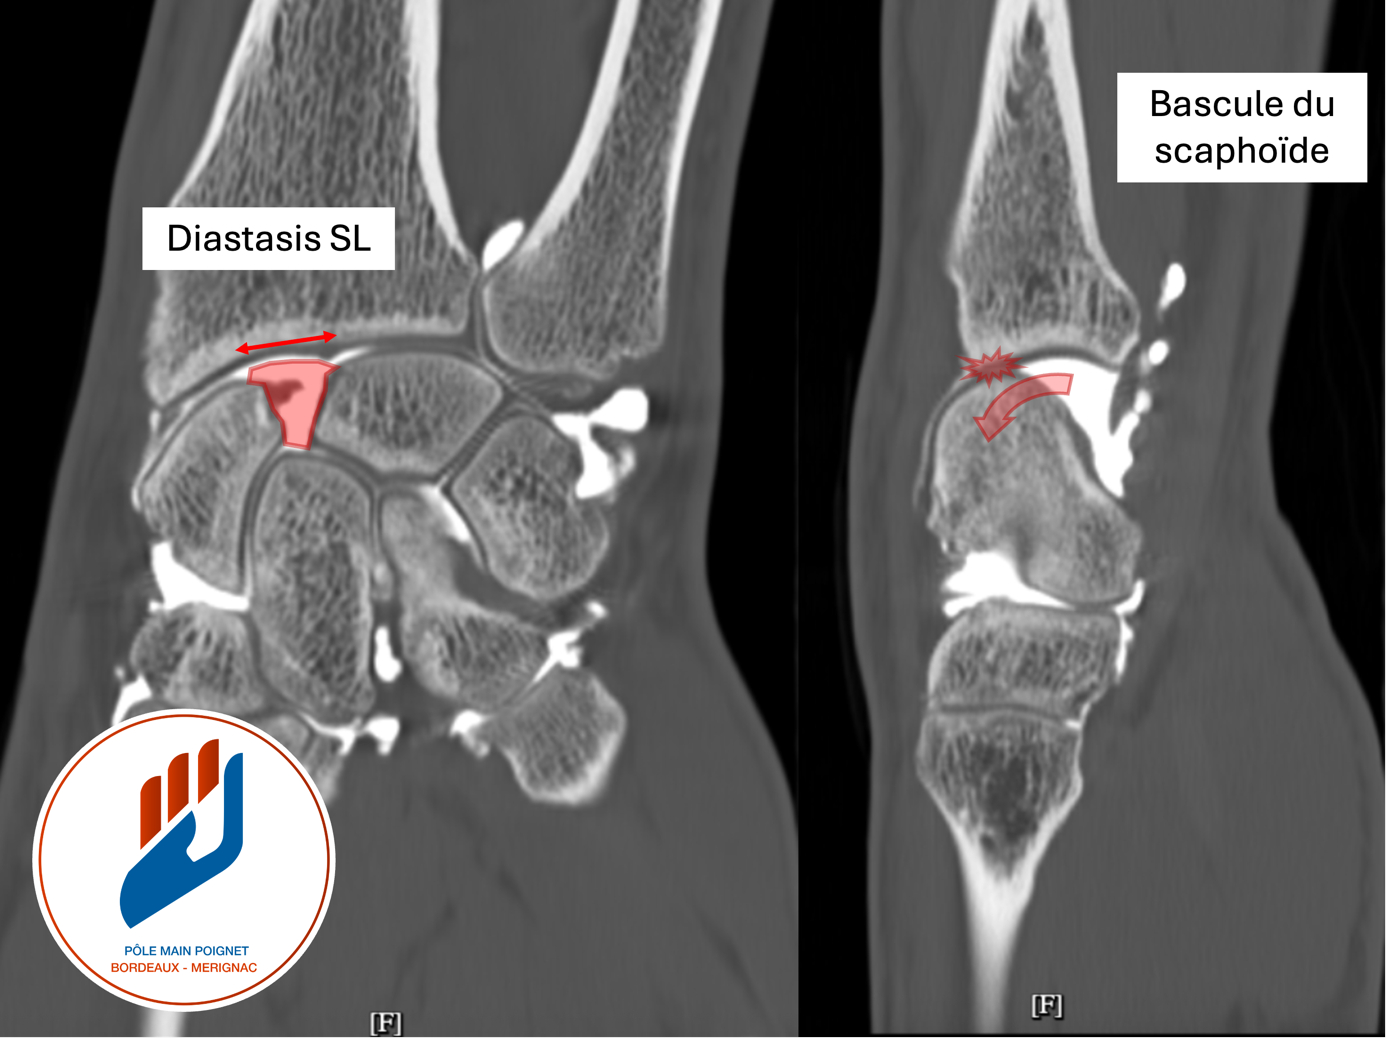

- Arthroscanner : il permet une analyse fine du cartilage, de la continuité ligamentaire et des structures capsulaires. Cet examen recherche spécifiquement :

- une subluxation postérieure du scaphoïde, témoin d’une perte d’alignement du carpe ;

- la mise en évidence d’une rupture du ligament scapholunaire, qu’elle soit partielle ou complète ;

- un diastasis scapholunaire statique, c’est-à-dire un écart anormal persistant entre le scaphoïde et le lunatum.

- Ces éléments traduisent une instabilité mécanique du poignet et orientent vers la stratégie thérapeutique la plus adaptée.

- L’arthroscanner permet également de dépister les complications liées à la subluxation postérieure du scaphoïde, notamment l’apparition d’une arthrose marginale postérieure radio-scaphoïdienne. Cette usure du cartilage, localisée entre le radius et le bord postérieur du scaphoïde, constitue le premier signe d’évolution vers une arthrose scapholunaire (SLAC wrist).